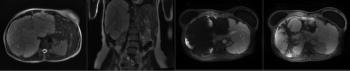

A 30-year-old female presents with right upper quadrant pain. An abdomen MRI is performed. What is your diagnosis?